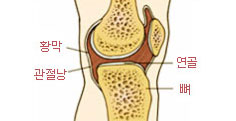

• 정상인의 관절 사진 (황막, 연골, 관절낭, 뼈)

정상인의 관절